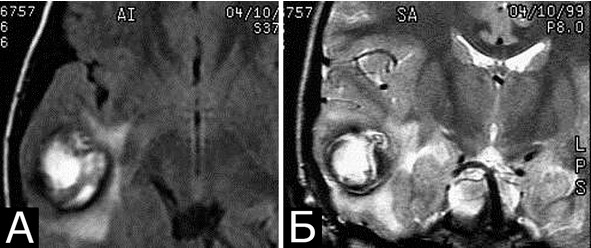

В отдаленном периоде в некоторых случаях можно обнаружить небольшие или достаточно крупные постгеморрагические кисты, прилежащие к каверноме (рис.36, А. Железнова). Признаком ранее перенесенных микрокровоизлияний служит наличие гемосидерина в окружающей каверному ткани, выявляемое при МРТ в виде ободка вокруг образования (рис. 36, Б).

Последний признак все же является косвенным, так как указанное кольцо может образовываться вследствие попадания крови в мозговое вещество per diapedesis.

Рис. 36. Варианты постгеморрагических изменений мозга вокруг кавернозной мальформации. А – множественные крупные постгеморрагические кисты вокруг каверномы правой теменно-затылочной области. Б – кольцевидные постгеморрагические изменения вокруг каверномы медиобазальных отделов правой височной доли. МРТ, режимы Т1, Т2